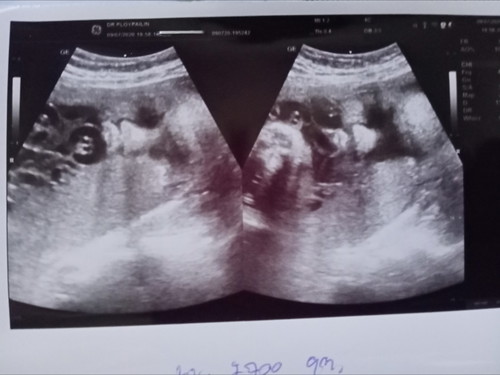

หมอบอกว่าลูกน้อยน้ำหนัก 2700กรัม แม่ๆว่าน้ำหนักน้อยไปรึเปล่าค่ะ แต่แม่บ้านนี้ว่ากำลังพอดีจะได้คลอดง่ายๆ